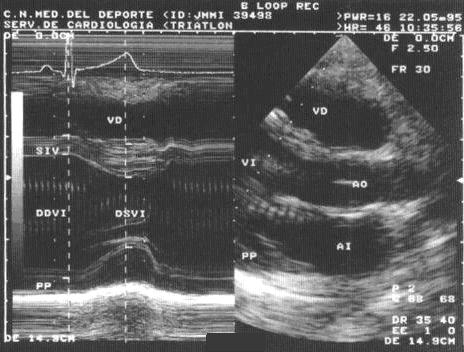

El corazón se adapta al estrés del ejercicio modificando su estructura y función para hacer frente a las exigencias de